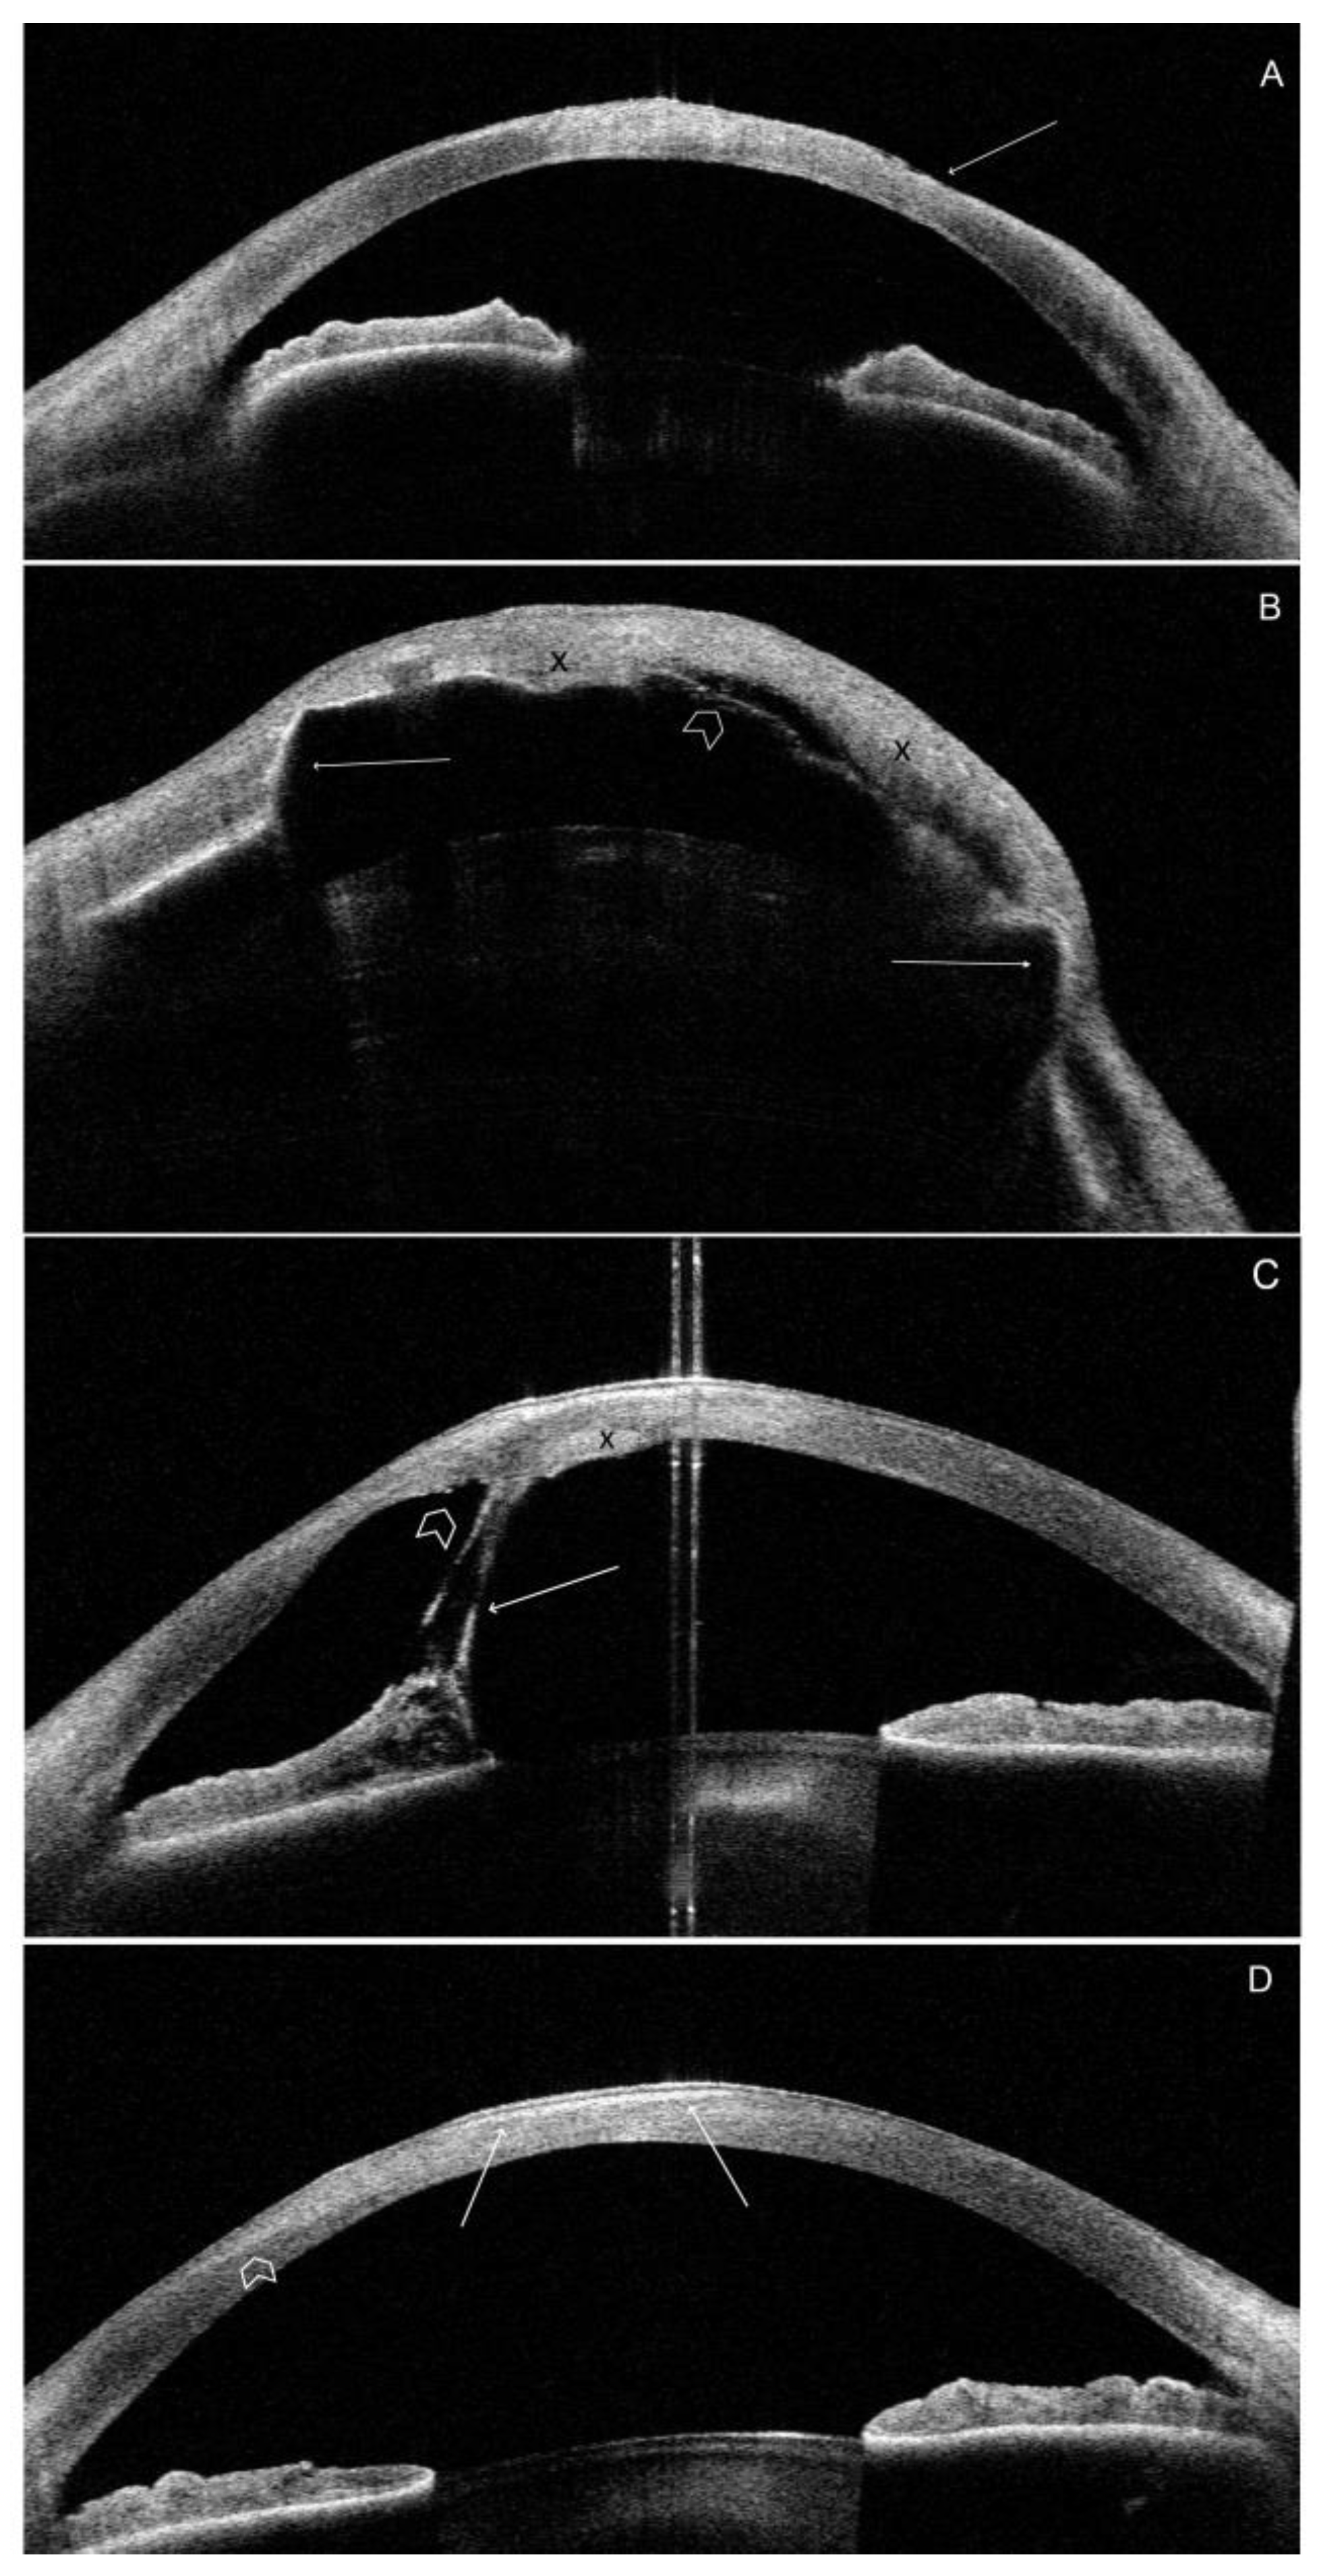

3.3. Optical Coherence Tomography

3.3.3. Morphology